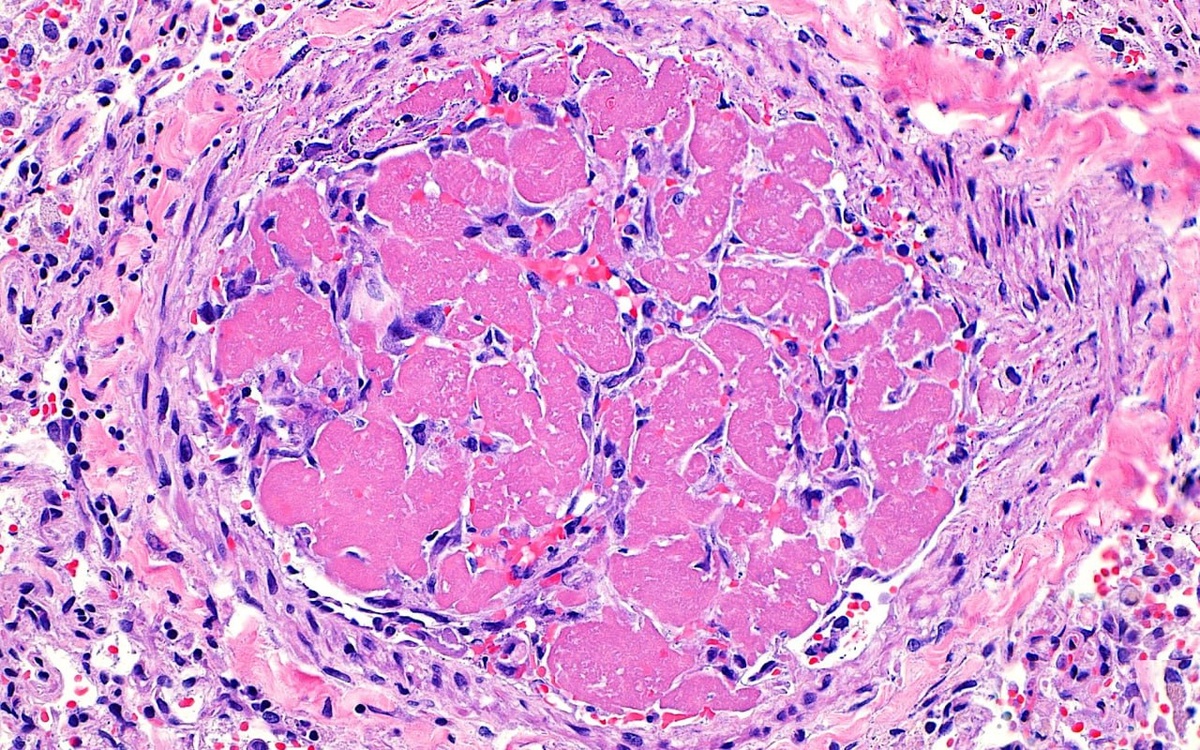

Тромб в кровеносном сосуде

Фибрин (ярко-розовый) и фибробласты (синие точки) в сосуде (крупная структура по форме близкая к окружности).